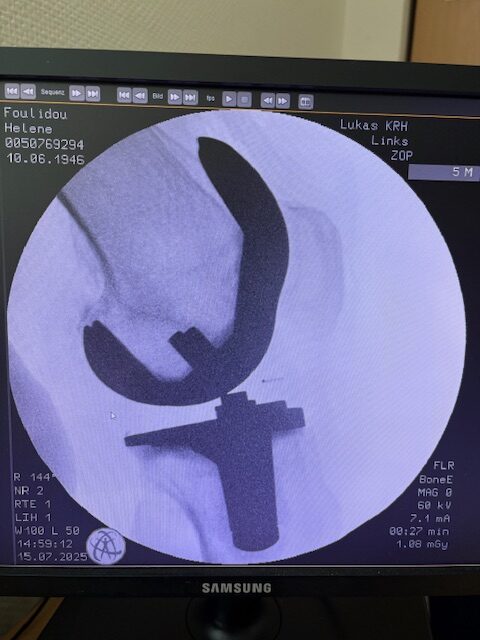

Η επέμβαση πραγματοποιήθηκε με ρομποτικά υποβοηθούμενη τεχνική, κατά την οποία το ρομποτικό σύστημα με καθοδήγησε με ακρίβεια χιλιοστού σε κάθε στάδιο.

Έτσι εξασφαλίστηκε η ιδανική τοποθέτηση των εμφυτευμάτων, η αποκατάσταση του μηχανικού άξονα και η διατήρηση των μαλακών ιστών.

Τα εμφυτεύματα που χρησιμοποιήθηκαν στο γόνατο της ασθενούς είναι της Aesculap: E-Motion Pro, μηριαίο μέγεθος 4, κνημιαίο μέγεθος 4, με ενθέμα (inlay) 10mm.

Η επέμβαση ολοκληρώθηκε χωρίς επιπλοκές, με ελάχιστη απώλεια αίματος και ταχεία κινητοποίηση της ασθενούς.